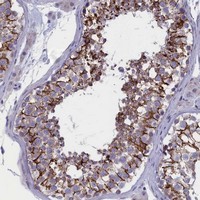

Supportive validation

- Submitted by

- Abnova Corporation (provider)

- Main image

- Experimental details

- Immunohistochemical staining of human testis with FAM129C polyclonal antibody (Cat # PAB24027) shows strong cytoplasmic and membranous positivity in cells in seminiferus ducts at 1:50-1:200 dilution.

- Validation comment

- Immunohistochemistry (Formalin/PFA-fixed paraffin-embedded sections)